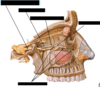

Label all:

Label all: